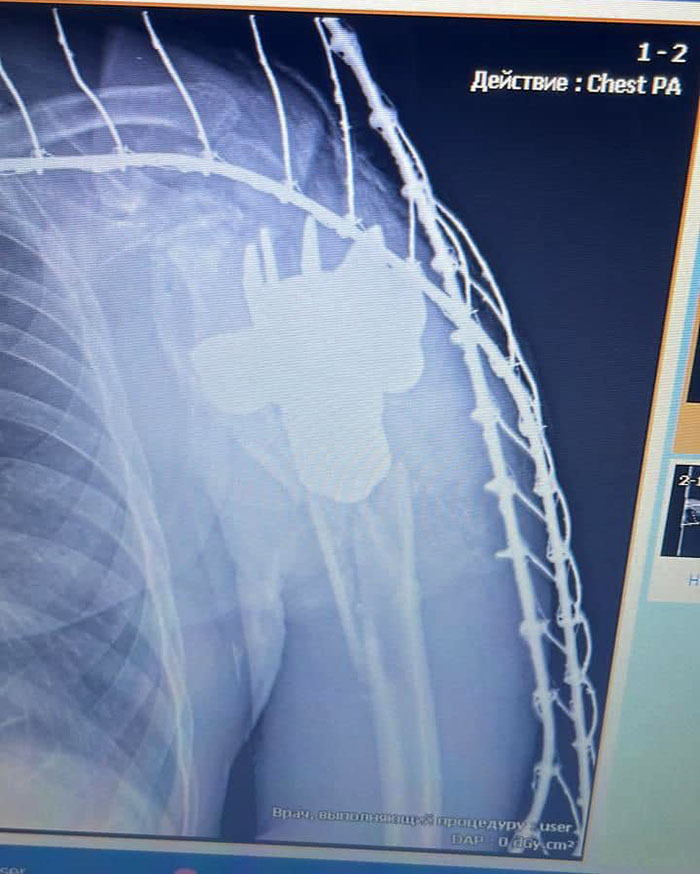

Про незвичайну ситуацію повідомило у Facebook Командування Медичних сил Збройних Сил України: при дообстеженні лікарями одного з прифронтових шпиталів, у тілі пораненого було виявлено сторонній предмет контури якого нагадували хвостовик міни.

На місце було викликано бригаду саперів, які після дослідження засвідчили, що сторонній предмет можна видалити безпечно.

Після дослідження, лікарями було прийнято рішення про оперативне втручання та видалення хвостовика.